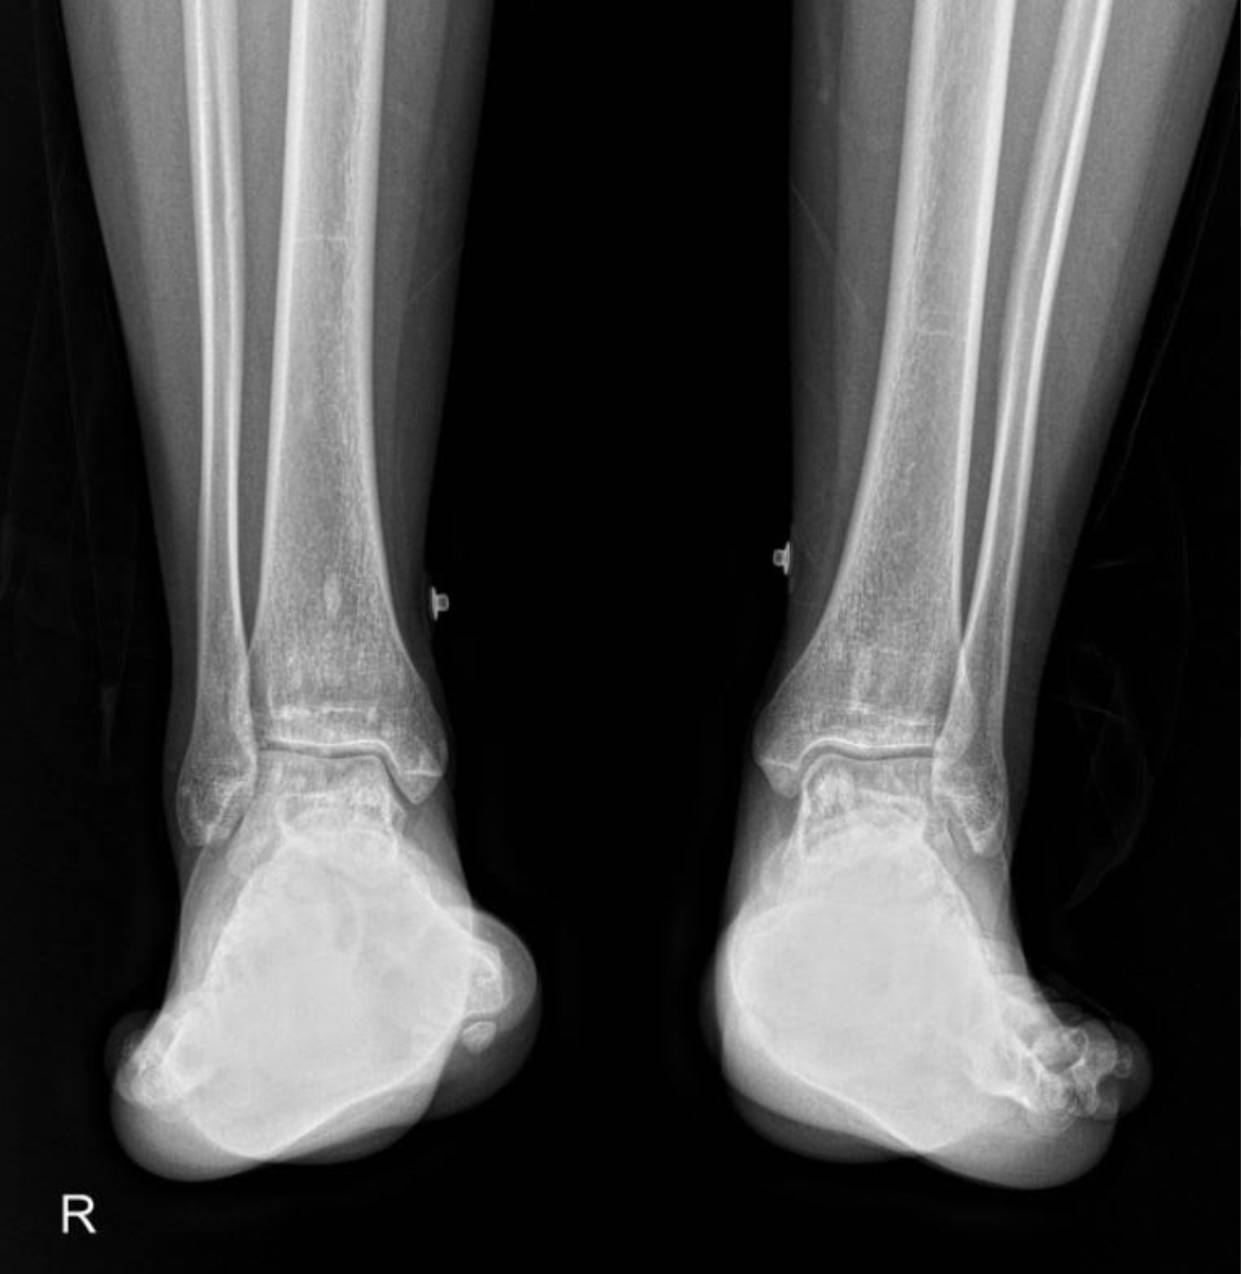

The X-rays of the pelvis, knees, elbows, wrists, and ankles demonstrate multiple, discrete, well-circumscribed sclerotic (densely opaque) lesions distributed symmetrically throughout the bones. These lesions are typically ovoid or spherical, varying in size, and are predominantly located in the epiphyses and metaphyses of long bones, as well as in the carpal and tarsal bones and the pelvic girdle.

Specifically:

- Ankles and Feet: The distal tibiae and fibulae, as well as the tarsal and metatarsal bones, show the characteristic sclerotic lesions.

These widespread, symmetrically distributed sclerotic bone islands are pathognomonic for hereditary osteopoikilosis (also known as osteopathia condensans disseminata). This condition is typically benign and often discovered incidentally. While not directly related to her renal artery stenosis or hypertension, its discovery is crucial for patient management as it can sometimes be associated with other connective tissue disorders, though often it is an isolated finding.